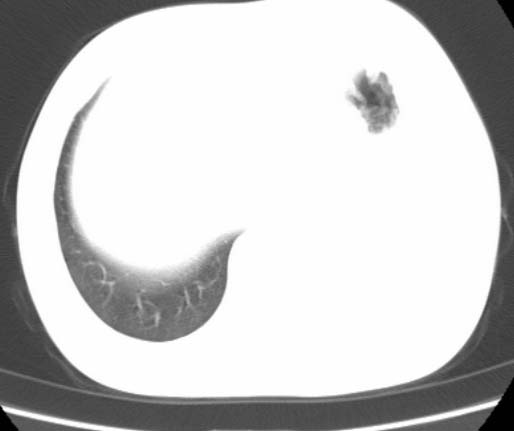

标题: CT25648:求教:是肺发育不全还是结核?

女  20岁。一月前咳血,诊“肺结核”抗痨治疗一月后,咳血停止,现复查。病人精神好。前后ct片对比未见明显变化。既往体检“正常”

1)考虑左肺结核并肺不张、支气管扩张。2)纵隔疝。

考虑左肺结核,左肺毁损,纵膈左偏,既往体检正常不可靠,tb一个月也不会这个样子的,有钙化,应该病程较长,冰冻三尺非一日之寒!

考虑左肺结核,左肺毁损,纵膈左偏,既往体检正常不可靠,tb一个月也不会这个样子的,有钙化,应该病程较长,冰冻三尺非一日之寒